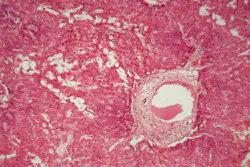

Amyloidosis is a rare but serious disease caused by the buildup of abnormal amyloid deposits in the body. The new guideline aims to support earlier and more accurate diagnosis, which is critical for effective treatment but has often been challenging for laboratories and pathologists.

- Congo Red Stain: Remains the standard for amyloid detection; other stains should be validated.